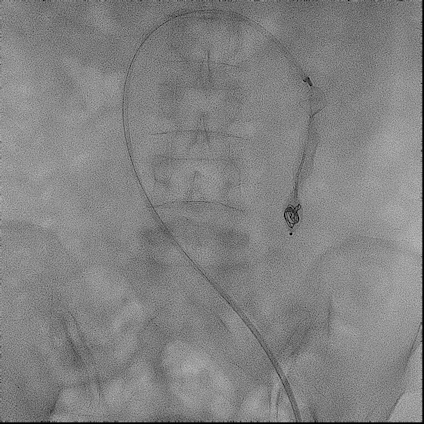

手术过程(二):

经8F鞘于A3段释放,“头端舱”锚定远端健康血管,使用导丝配合AVP可以完整覆盖动静脉瘘段,16mm AVP Ⅱ形态良好,Renegade微导管经18导丝送入网盘“中间舱”,仍可见明显分流。